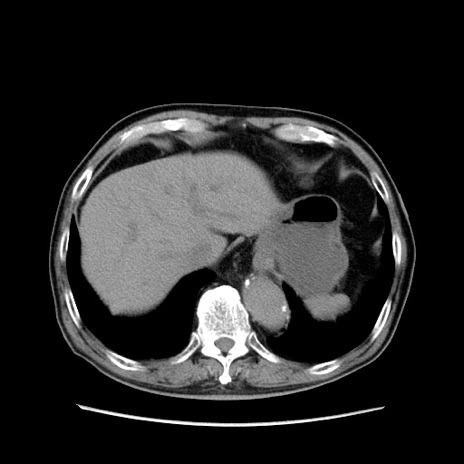

症例24(横断像)

【症例】80歳代男性

【主訴】左側腹部痛、嘔吐

【現病歴】本日早朝より左腹部に痛みあり。昼頃嘔吐認めたため、救急要請。

【既往歴】直腸癌(Mile手術)、胆摘

【身体所見】意識清明、BT 35.9℃、BP 221/93mmHg、SpO2 97%(RA) 、腹部:左ストーマ周囲に限局性の腹部膨隆あり。 膨隆部自発痛・圧痛あり・軟。

【データ】WBC 7700、CRP 0.09